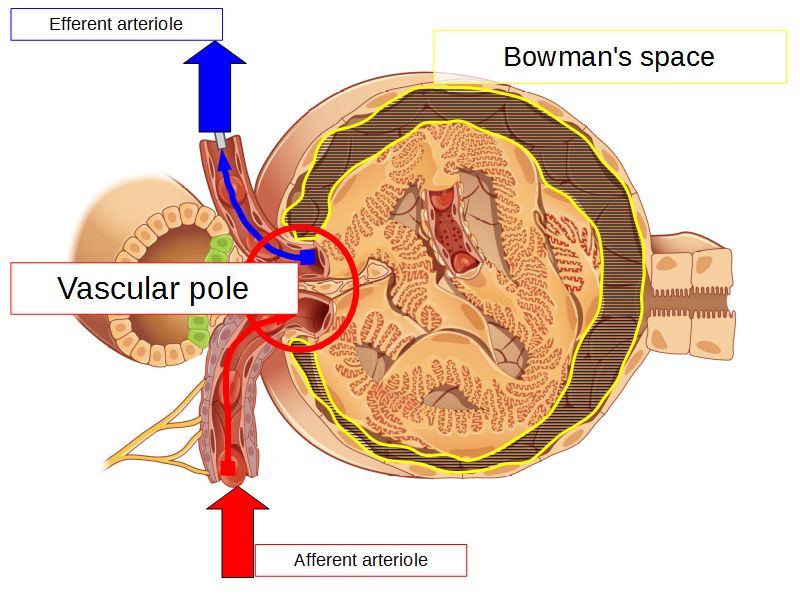

Renal corpuscle

- Tuft of capillaries

- grow into

- Blind end of nephron

- Several layers of epithelium

- Two sides

- Vascular pole

- Tubular pole

Blood flow

- Efferent arteriole

- Smooth muscle in media

- Capillaries

- Fenestrated

- Afferent arteriole

- Smooth muscle in media